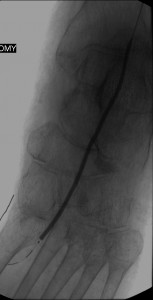

After instituting strategies to minimize contrast-induced nephropathy, I employed atherectomy of the distal LSFA and popliteal stenoses and angioplasty of the multifocal stenoses of her anterior tibial artery down to the dorsalis pedis artery to restore reasonable flow to her foot that helped the ulcer heal.

Images in the top panel illustrate her disease before the interventions, those in the middle panel illustrate some intraprocedural steps (balloon angioplasty), while those in the bottom panel illustrate improved blood flow to the foot following treatment.